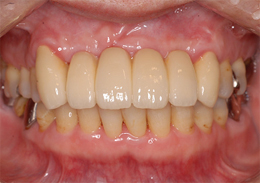

ボーングラフトインプラント(ブロック骨移植をし骨造成をしたインプラント)

ボーングラフトは、十分な量の骨が得られない場合に、骨をブロックで切り出し、移植することで必要な骨を作り出します。

- 主訴

- 上顎前歯の噛む時の痛み

- 治療内容

- 上顎前歯部を抜歯すると大きな骨吸収を予測したため、下顎臼後三角部より骨片を採取し、抜歯時にインプラント埋入と同時に骨造成を行なった

- 治療費用

- 800,000円(税別)

- 治療期間

- 5ヶ月